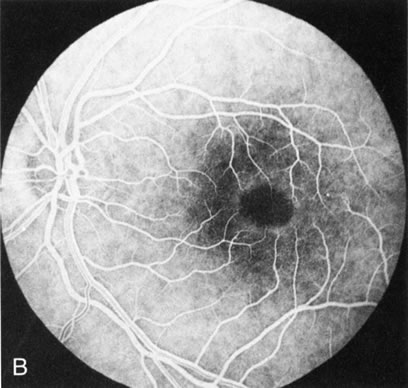

When the macula has typical superficial linear plications radiating from the fovea seen with schisis (e.g., juvenile retinoschisis, Goldmann-Favre disease), FA is normal (Fig. 8A and B). This indicates that the pathology is in the inner retina (probably Henle's fiber layer, considering the spokewheel pattern). However, when the schisis flattens, it is not uncommon to see a transmitted hyperfluorescence suggesting a secondary atrophy to the RPE (Fig. 8C and D).

Fig. 8. Juvenile XLR retinoschisis. The superficial macula schisis (A) does not affect the angiogram (B) except in a few areas where it has flattened and resulted in some pigment dispersion. When the macular schisis has entirely flattened (C) there is a mild transmission hyperfluorescence (D). At this stage the diagnosis can be suspected by the presence of an inferior retinoschisis (present in half) and confirmed by the typical electroretinographic finding of a scotopic electronegative response (present in all affected males).

The periphery may show schisis or vascular sheathing. Histopathology of the peripheral schisis in juvenile retinoschisis documents a splitting of the nerve fiber layer.13 FA shows retinal vascular abnormalities, including capillary nonperfusion, focal and diffuse vascular leakage, and intraretinal neovascularization, in many of these disorders.14 These may or may not be associated with schisis.

As with generalized tapetoretinal dystrophy (RP), FA clearly delineates retinal vascular decompensation in some of these patients. What remains to be answered is whether this is part of the basic disease process or a secondary reaction to it.